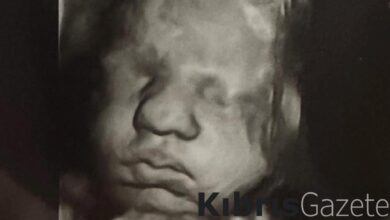

ABD’deki çift rahimli kadın aynı anda iki farklı bebeğe hamile kaldı!

ABD’de alışılmışın dışında bir olay yaşandı. Kelsey Hatcher isimli bir kadın, doğuştan çift rahmi olduğunu ve...

ABD’deki çift rahimli kadın aynı anda iki farklı bebeğe hamile kaldı

Kelsey Hatcher isimli bir kadın, doğuştan çift rahmi olduğunu ve nadir görülen bir hamilelikle her iki rahminde de kız bebek…